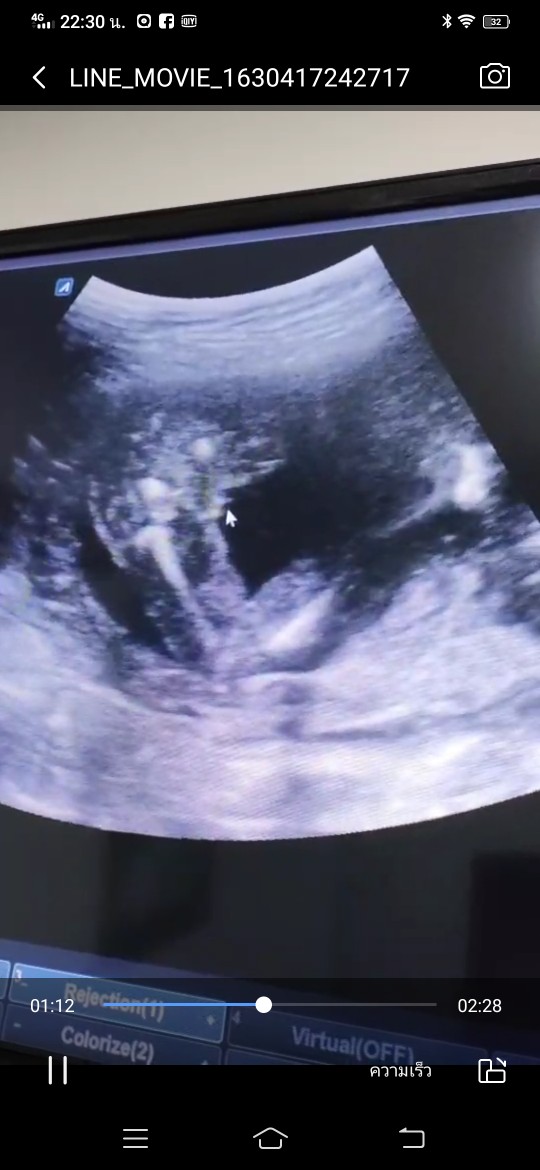

ชายจ้า ชัดมากๆมาเปนพวง😆😆

ได้ลูกชายจ้าา ทีมมกราคม 65

บ้านนี้ ลูกชายคนแรกค่าาา

ซาวด์ตอน27weekจ้า ผู้ชาย_จ้า